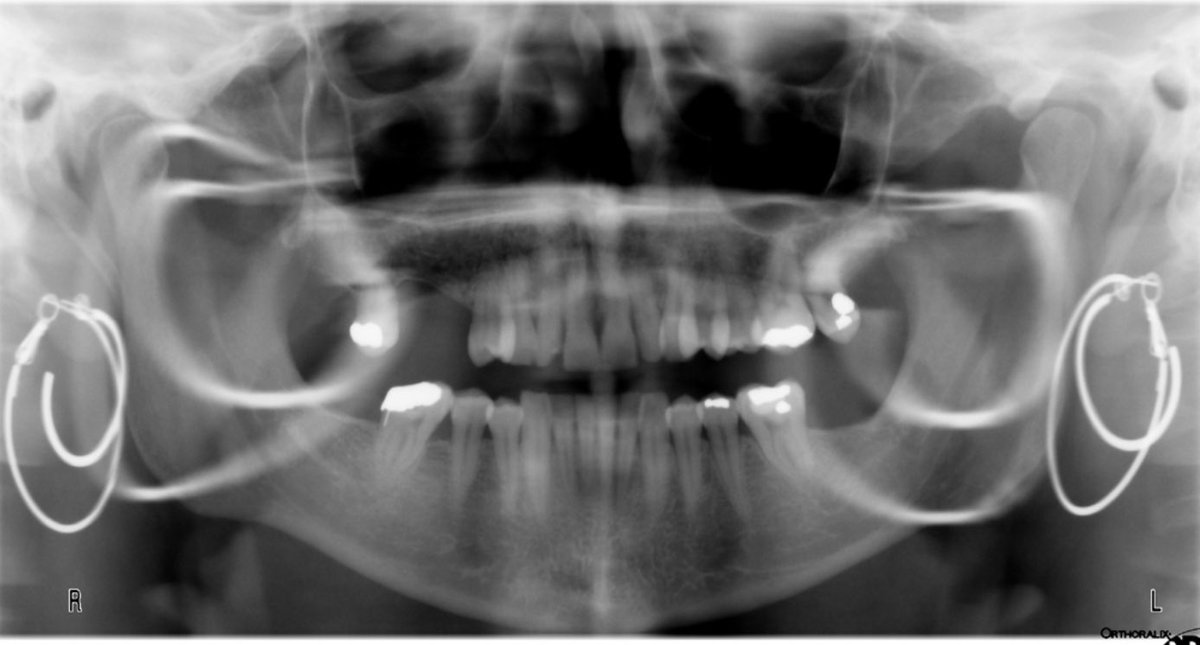

النوع الثالث:وهوالاشعة البانورامية وتسمى أيضا Orthopantomogram (OPG)

وهي الاشعة التي تدور حول رأس المريض لتعطي صورة شاملة للاسنان والأنسجةالمحيطةوالجيوب الأنفية ومفصل الفك والفكين واستخداماتها منها:

-نظرة شاملةلحالة الفم ليتسنى عمل خطه علاجيه وعند الحاجه يستعان بالأشعة الصغيره

وتستخدم:

-لتقييم وضع ضرس العقل المدفون وعلاقته بالأنسجة الحيوية الاخرى مثل عصب الفم

- لتقييم حالة العظم والأنسجة المحيطة لوضع زرعة سنية

-تشخيص الأمراض والالتهابات التي تصيب الفكين

-كسور الفك

-تشخيص قبل وخلال وبعد تقويم الاسنان بالاضافة الى اشعة اخرى

-مشاكل مفصل الفك

وأشعة البانوراما 👇 تطورت اجهزتها مع مرور الزمن لكن مازالت لاتعادل الاشعة الصغيره PA لذلك لا تستخدم بشكل روتيني ويومي وإنما للحاجه كما ذكرنا سابقاً

فهي لاتستخدم مع علاج العصب او تحديد التسوس بين #الاسنان

وقد تستخدم قبل وبعد (وخلال ان دعت الحاجه) التقويم